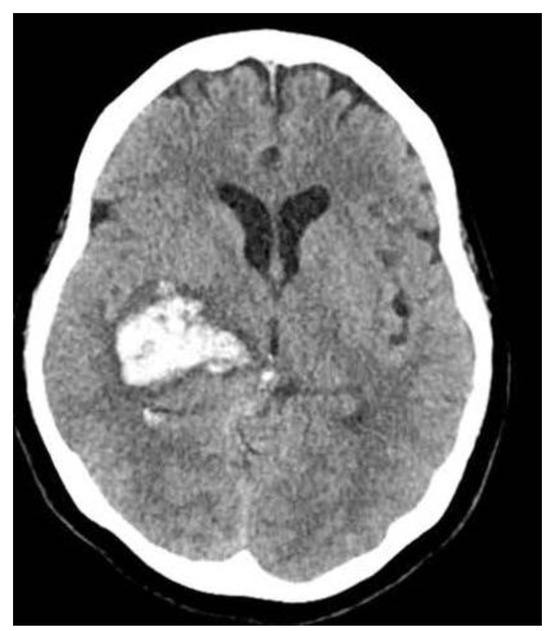

Introduction: Thrombotic thrombocytopenic purpura (TTP) is a thrombotic microangiopathy associated with severe ADAMTS13 deficiency that can be potentially fatal if not treated in a timely manner. Case report: A 49-year-old previously healthy woman was admitted with a 3-month history of thoracoabdominal pain and headache associated with loss of appetite, emesis, nocturnal diaphoresis, and unintentional loss of 10 kg. On admission she presented anemia, thrombocytopenia, schistocytes in peripheral blood smear, and ADAMTS13 in 1.4%. Due to laboratory findings a diagnosis of TTP was established, and plasma exchange therapy and steroid pulses were started, with resolution of hematological alterations. Within the studies to determine etiology of TTP, pulmonary tuberculosis (TB) was found, neoplastic and autoimmune pathologies were excluded. The tetraconjugated treatment was initiated with optimal tolerance. Conclusions: Upon clinical suspicion of TTP, plasma exchange therapy should be initiated urgently; infectious, neoplastic, or autoimmune pathologies can be triggers; in this case, pulmonary TB was confirmed. Full article

Show Figures

Figure 1